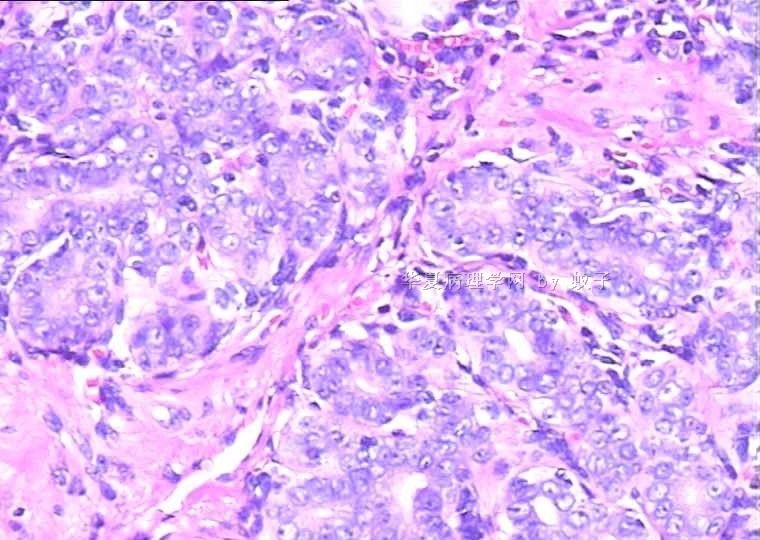

B2156乳腺活检

姓    名: ××× 性别:  女 年龄:  20

简要病史:  右乳包块8年。

肉眼检查:  灰白不整形组织一块,切面灰白,灰红,实性,质韧。

• 乳腺活检图1

图1

标签:乳腺腺病

旺识型腺病

有包膜吗?良性,首先考虑纤维腺瘤(图5、6透明变的纤维支持),其次腺瘤。

无明显包膜,界限较清,

我们考虑腺瘤,(图5,6为混有纤维瘤组织)

腺病瘤(主要成份旺炽性腺病)部分区域为纤维腺瘤(管内型)